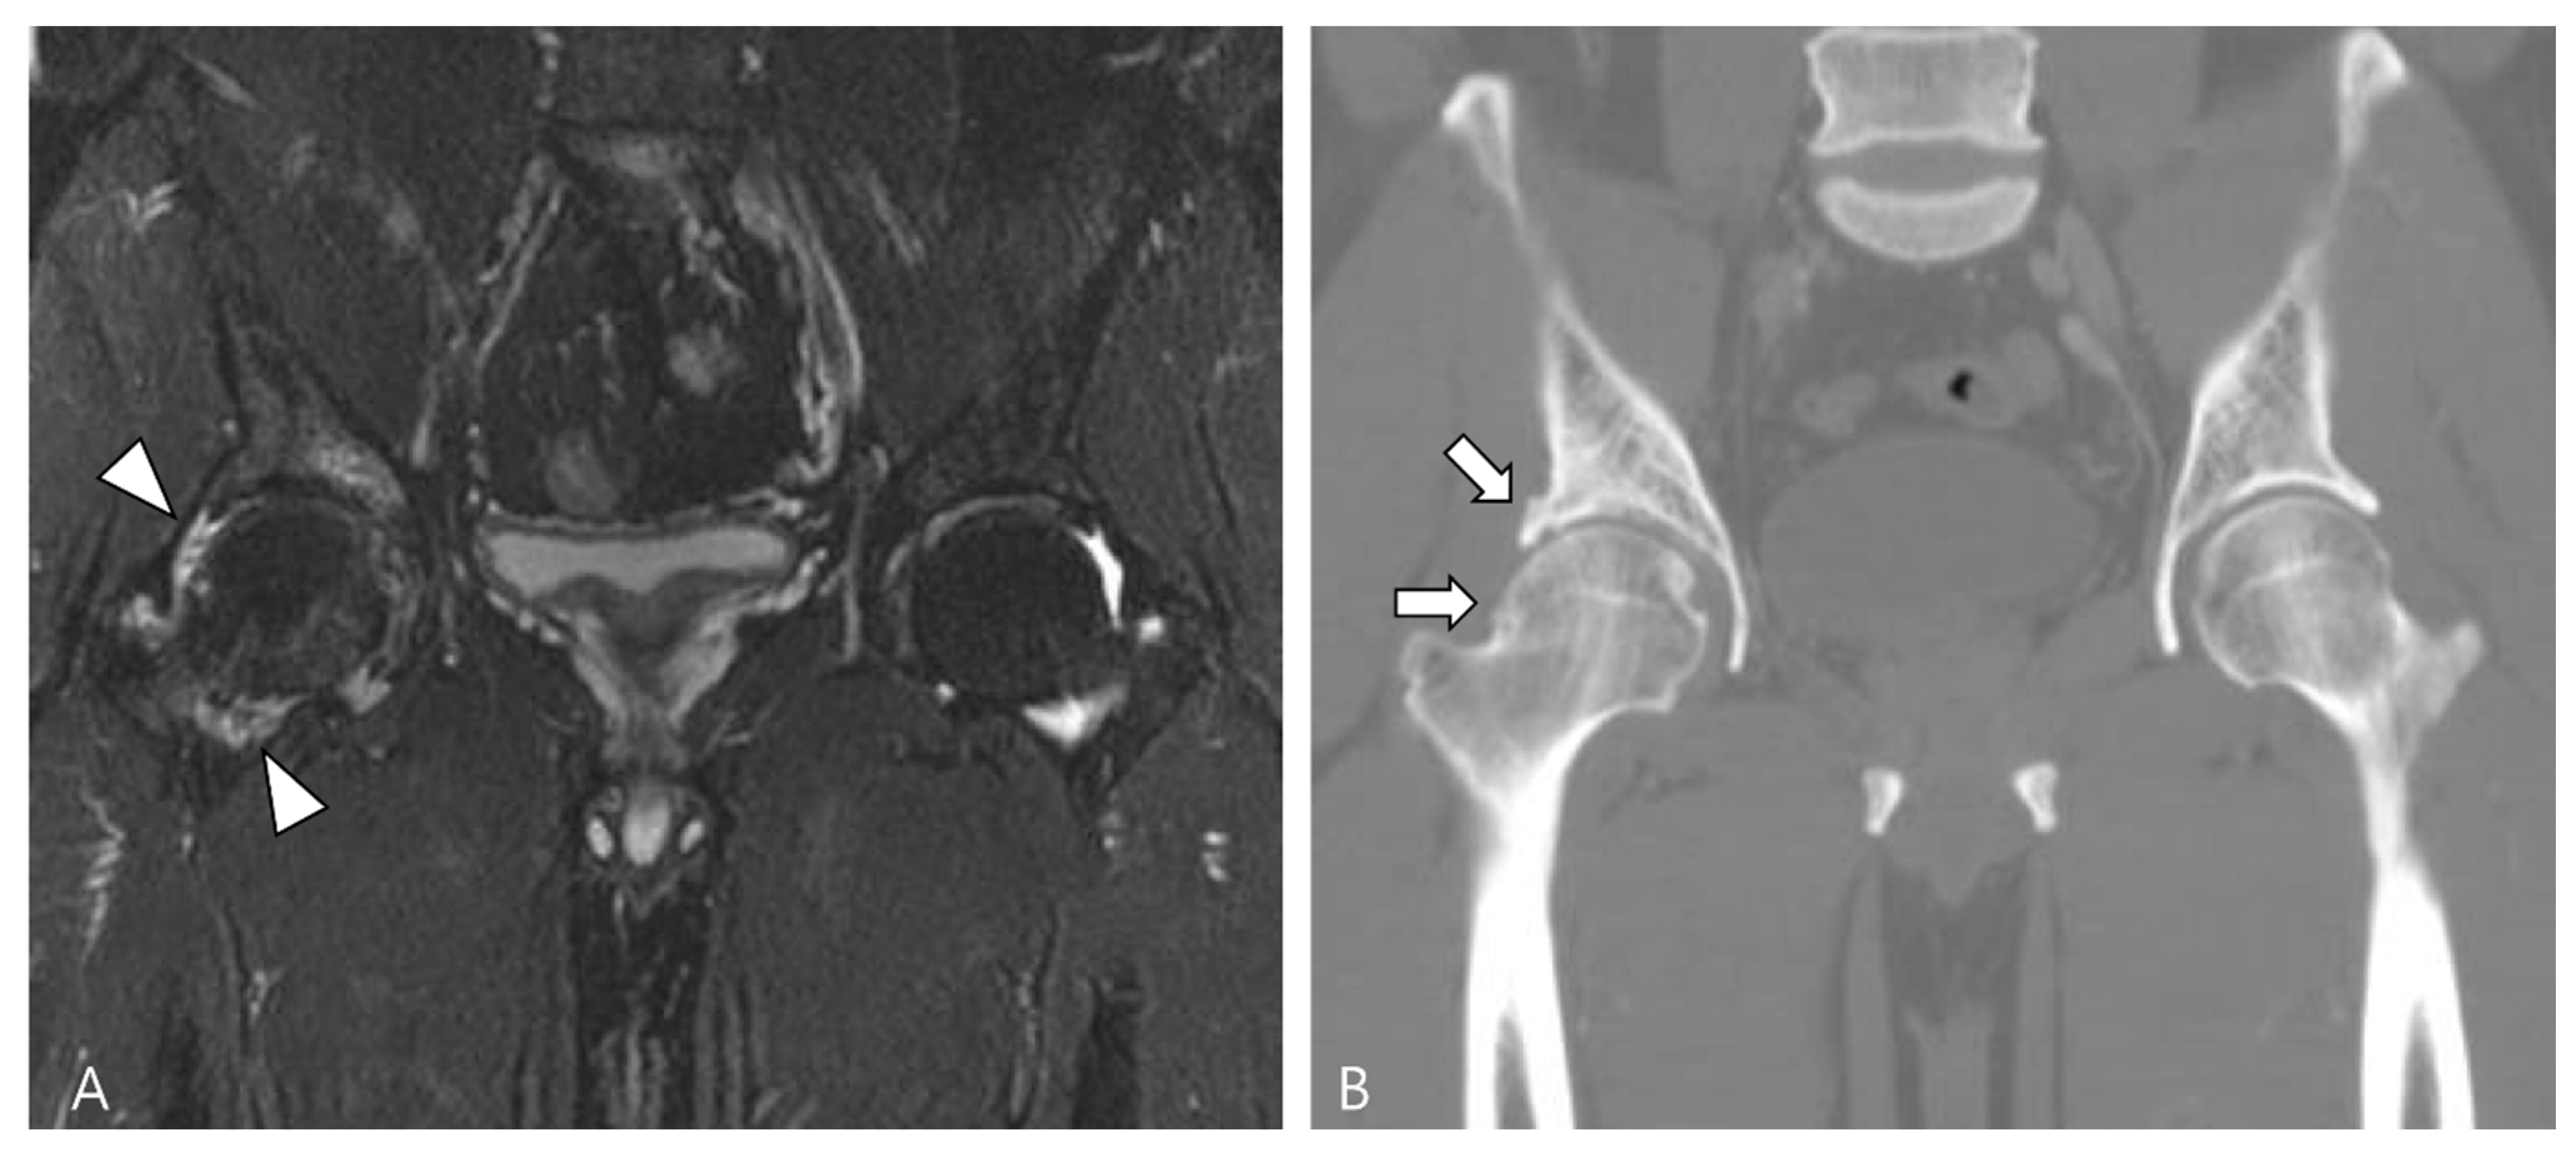

D-TSGCT also poses a risk for the early development of osteoarthritis, particularly in the knee, hip, and ankle [80]. Recurrent disease is likely to necessitate multiple surgeries, leading to significant joint morbidity that could expedite the degenerative process associated with D-TSGCT toward secondary osteoarthritis (Figure 19) [81]. Lin et al. [81] reported that nearly 30% of patients underwent at least two surgeries during follow-up, and the risk of recurrent surgery was twice as high in patients with osteoarthritis compared with those without. This underscores the imperative for effective non-surgical treatment options for D-TSGCT, especially in patients with secondary osteoarthritis [81].

Figure 19.

A 47-year-old male with D-TSGCT in the right hip joint. (A) Initial coronal fat-suppressed T2WI shows a tiny low SI nodular synovial thickening in the right hip joint (arrowheads). (B) After synovectomy, follow-up CT after 4 years shows the development of osteoarthritis (arrows) in the right hip joint.